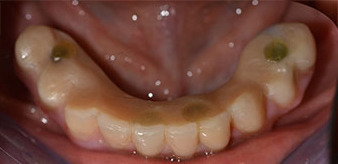

Пациентката е 64-годишна жена с частично обеззъбяване на зъби 38, 33 и 43 и частична долночелюстна протеза (Фиг. 1 и 2).